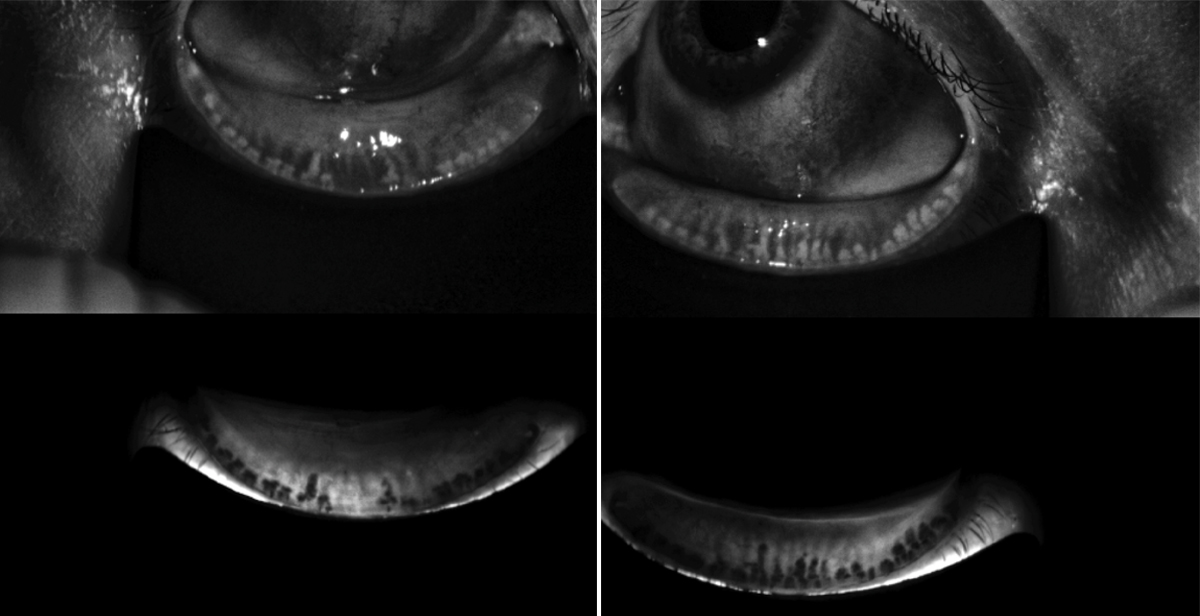

For all positive questionnaires, our clinic performs tear osmolarity testing using the TearLab Osmolarity System (TearLab). We emphasize identification of meibomian gland dysfunction (MGD), which can change the patient’s refractive measurements, topography measurements, biometry measurements, and may cause dry eye.1 Meibum that is thin and oily indicates healthy meibomian gland function, whereas toothpaste-like expression indicates that a gland is likely impacted and will require intervention. We perform meibography using either LipiScan (Johnson & Johnson Vision) or LipiView (Johnson & Johnson Vision) in patients with suspected impacted meibomian glands (Figure 2). Other meibography options include the Meibox (Box Medical Solutions) and the Meibo-scan function on the Keratograph 5M (Oculus).

Figure 2. A meibography image of a patient with advanced MGD and gland atrophy.